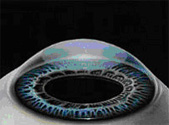

The cornea is a transparent curved lens at the front of the eye. It bends light onto the back of the eye so that a clear image can be produced on the retina. By reshaping the cornea with a Solid State laser it is possible to adjust the focusing power to improve unaided vision.

Trans-Epithelial Surface Treatment is an advanced form of surface laser treatment.

Trans-Epithelial Surface Treatment is performed in two stages:Firstly, the laser is used to ablate the corneas surface layer with pinpoint accuracy and regularity. Secondly, the laser is programmed to remove exactly the right amount of corneal stromal tissue to achieve the shape change required from the cornea to improve your vision. Following treatment a bandage contact lens is placed over the cornea for a few days as the epithelial layer heals.